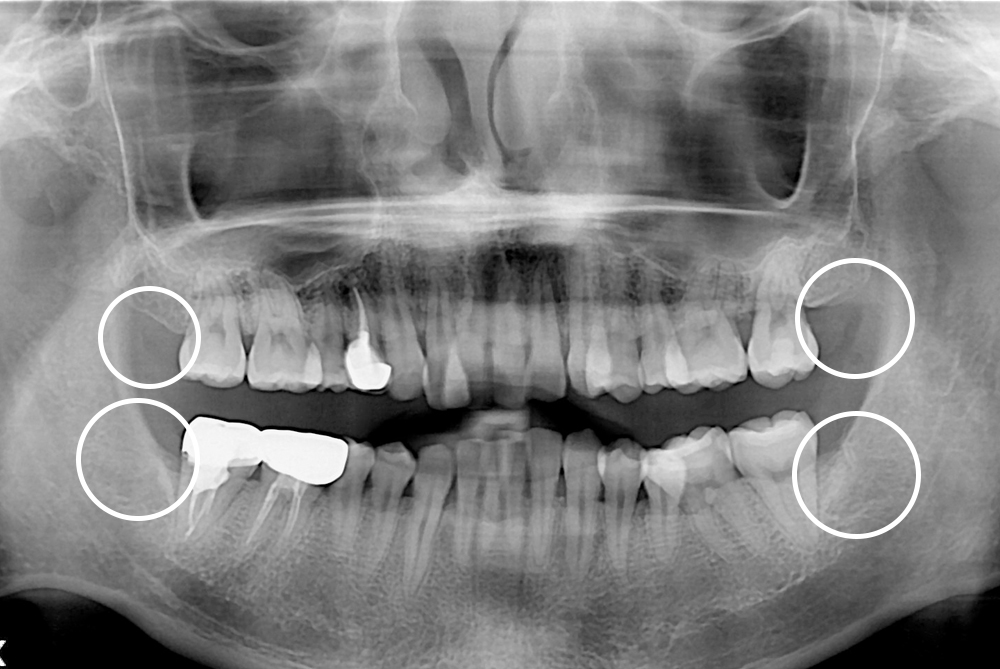

[사랑니] 매복 사랑니 발치

치료후 : 2019-04-15

세종치과는 구강악안면외과학 박사이신 원장님이 발치하는 치과입니다.